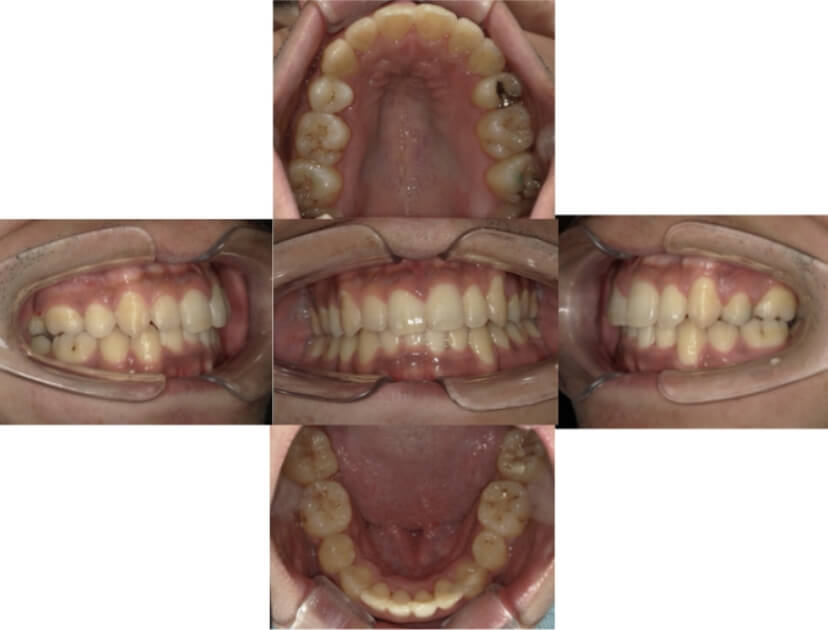

BEFORE

AFTER

上下顎叢生(上下の前歯のガタガタ)のケースです。

装置はラビアル(上下表側)で、上下顎の小臼歯を4本抜歯を行っています。抜歯したスペースを使って、上下の前歯の後方移動と叢生(ガタガタ)の改善を行っています。

主訴 八重歯を治したい。

年齢・性別 25歳 女性

お住まいの地域 神奈川県川崎市

治療方針 抜歯スペースを利用して上前歯の叢生(ガタガタ)の改善

抜歯部位 上下顎左右第一小臼歯

使用装置 ラビアル(上下表側)、顎間ゴム

治療期間 1年11か月

治療回数 16回